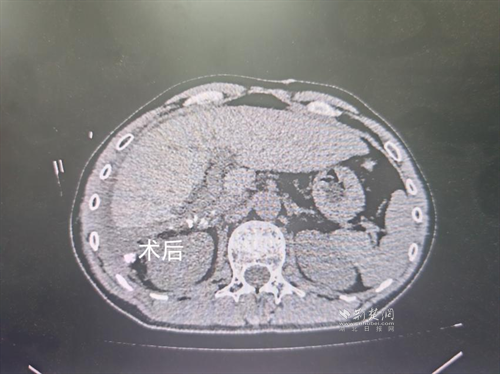

經(jīng)過(guò)肝膽外科牽頭組織的多學(xué)科MDT會(huì)診,團(tuán)隊(duì)確認(rèn)其適合接受當(dāng)前國(guó)際先進(jìn)的釔90樹(shù)脂微球選擇性內(nèi)放射治療。治療僅一個(gè)月后,患者病灶即從10cm縮小至6cm;術(shù)后六個(gè)月復(fù)查顯示,病灶體積進(jìn)一步縮小近40%,影像學(xué)檢查提示完全緩解,臨床分期成功轉(zhuǎn)化,達(dá)到手術(shù)切除標(biāo)準(zhǔn)。